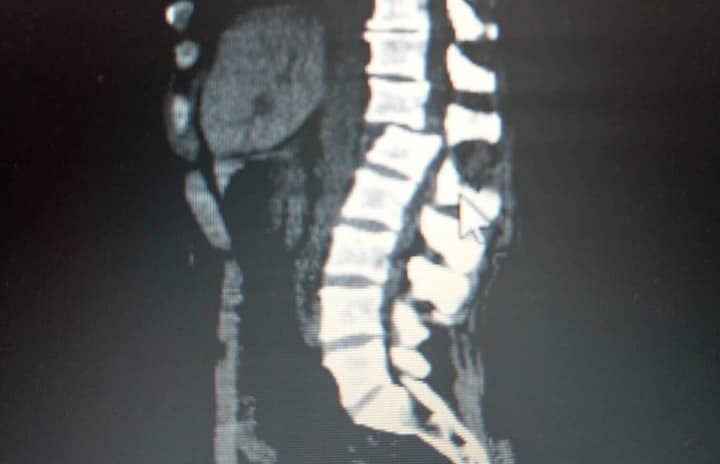

В резултат на това, Йоско получи множество тежки травми – разкъсвания на бял и черен дроб, черепно-мозъчна травма и счупване на гръбначния стълб.

В момента Йоско е в УМБАЛ "Канев" - Русе, обездвижен и под медикаментозно лечение. На 25 юли ще бъде транспортиран в болница Токуда в София, където ще му бъде направена спешна операция.